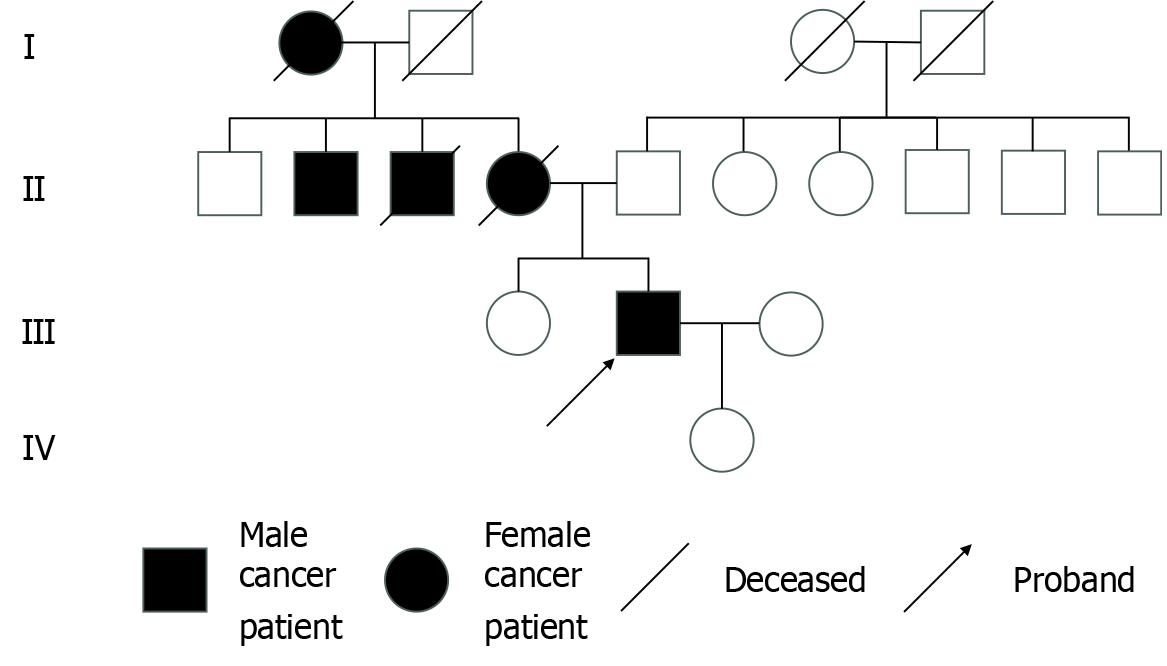

The patient’s family history was significant for colon cancer, with his mother and maternal uncle both having been diagnosed and deceased due to the disease (Figure 1).